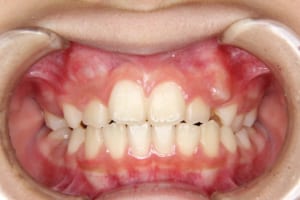

After

治療後

| その他/備考 | 上の犬歯が生えるためのスペースが全くない状態でした。放置すると重度の八重歯になることが想定されるケースです。 今回はあごの成長も利用しながら治療をするために、早めに後期治療(大人の矯正治療)に移行しました。 治療後レントゲン写真を見たところ、上顎前歯に若干の歯根吸収を認めました。 |